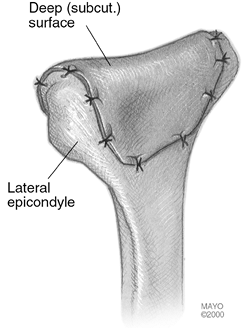

![]() |

Figure 22-3. An extensile Kocher approach to the posterolateral aspect of the elbow is preferred.

Figure 22-9. A,B:

The ipsilateral anterolateral aspect of the abdomen is exposed and a motorized dermatome removes a thin, 10- to 12-mil split-thickness skin graft. |

Figure 22-16.

The cutis graft is then applied to the distal humerus with the superficial aspect of the dermis applied to bone and the deep or subcutaneous surface exposed to the proximal ulna. The graft is held in place with multiple sutures placed through bone. |

Figure 22-17. The graft completely covers the distal humerus.